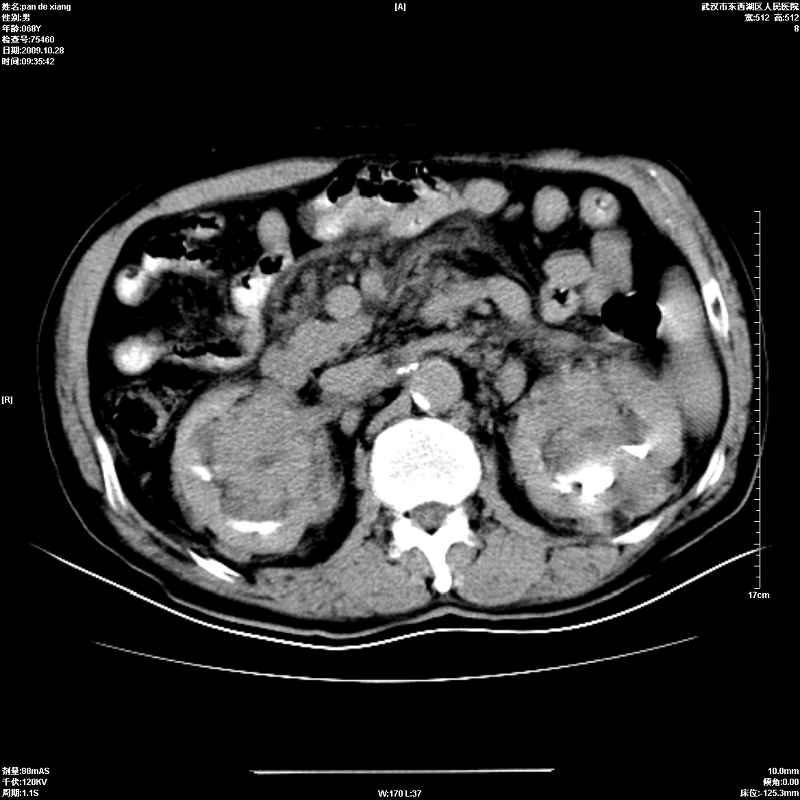

以下是引用杀毒软件在2009-10-28 20:41:00的发言:[br]结合临床考虑---白血病双肾改变或淋巴瘤。

以下是引用zxl51642在2009-10-29 9:59:00的发言:[br]结合临床“单克隆免疫球蛋白血症”,考虑双肾为继发损害并肾功能不全(尿中大量igg及少量iga、igm等大分子免疫球蛋白滤出所致继发损害),椎前软组织肿块为髓外造血。与浆细胞瘤有区别,平扫时有战友说的很清楚。